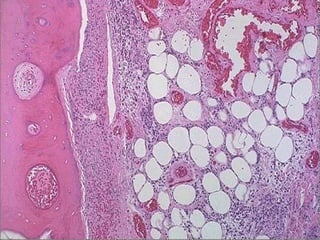

Caseous Necrosis

• Gross: Resembles cheese

• Micro: Amorphous, granular eosinophilc

material surrounded by a rim of

inflammatory cells

– No visible cell outlines – tissue architecture

is obliterated

• Usually seen in infections (esp.

mycobacterial and fungal infections)

Caseous necrosis -- micro

Caseous Necrosis • Gross:Resembles cheese • Micro: Amorphous, granular eosinophilc material surrounded by a rim of inflammatory cells – No visible cell outlines – tissue architecture is obliterated • Usually seen in infections (esp. mycobacterial and fungal infections)